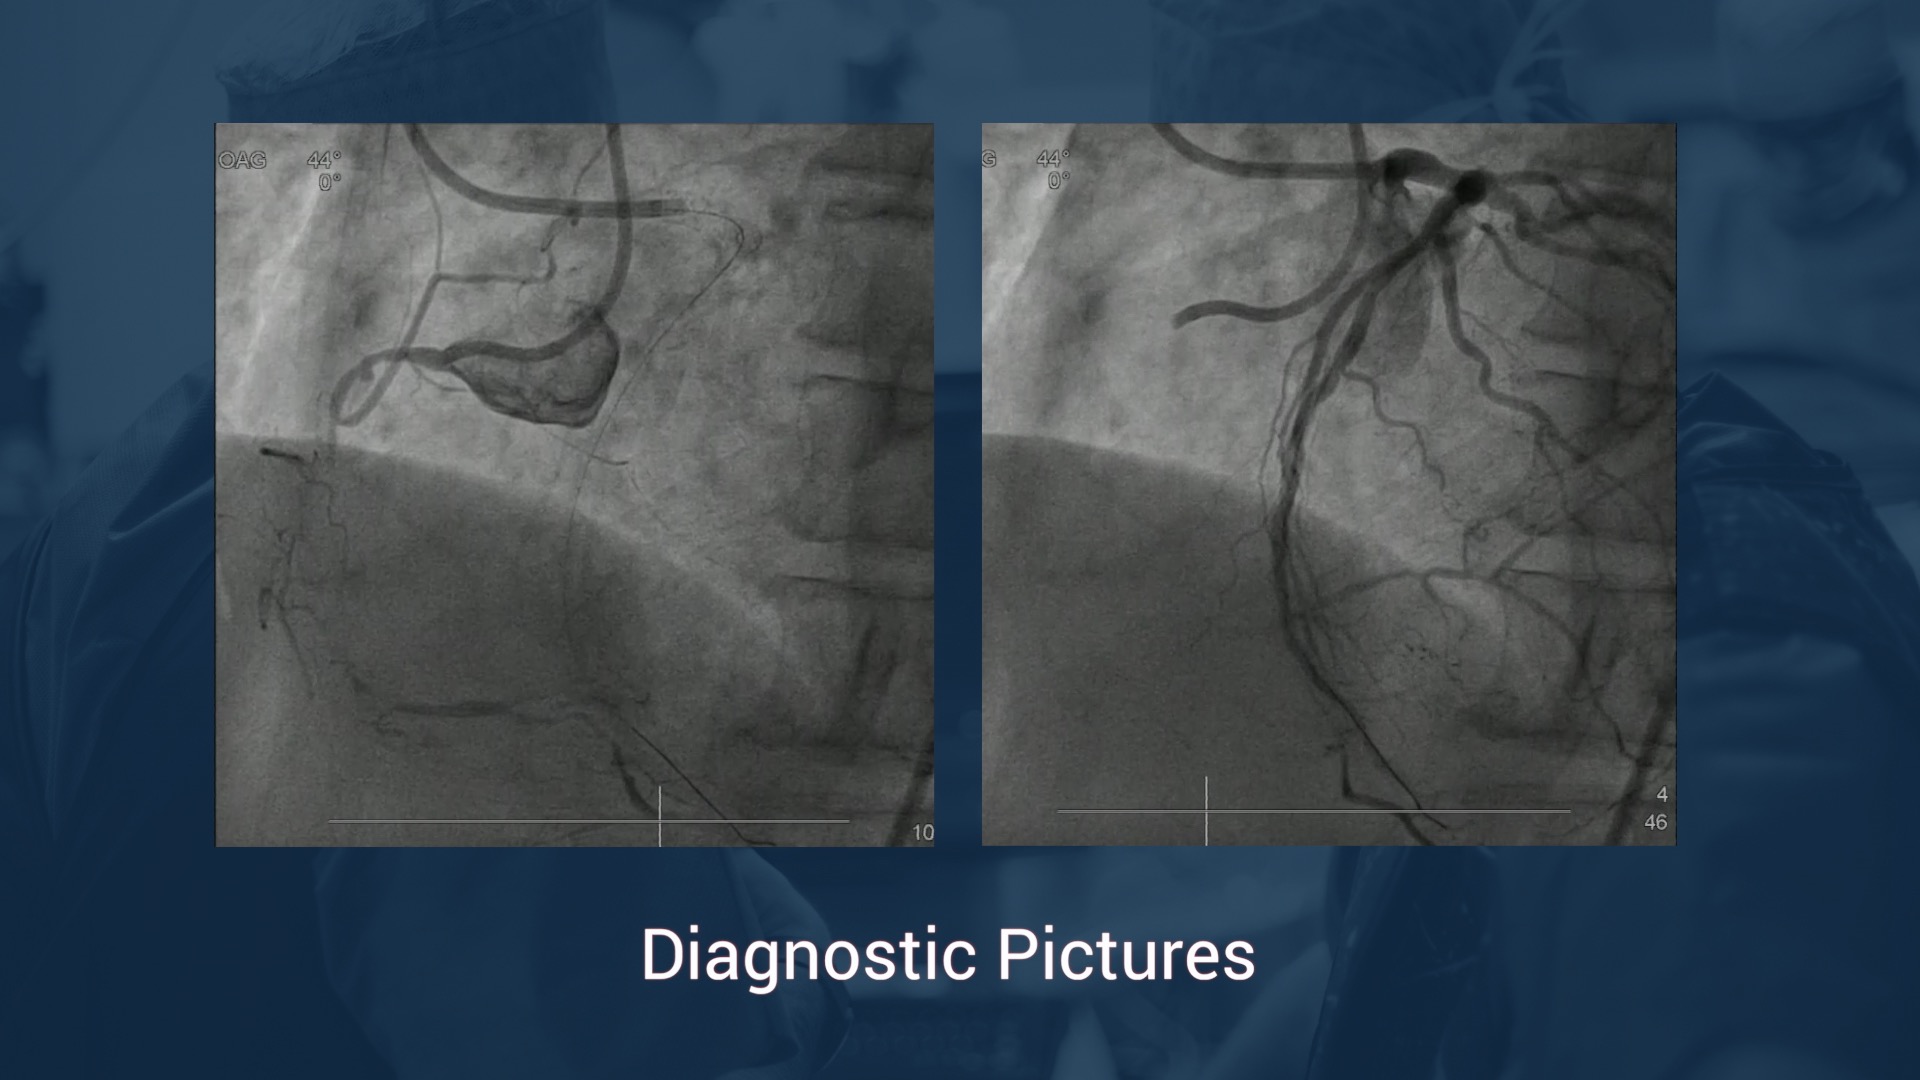

• Coronary angiography: LAD Prox 75%, LAD mid :100%, RCA mid: 75%